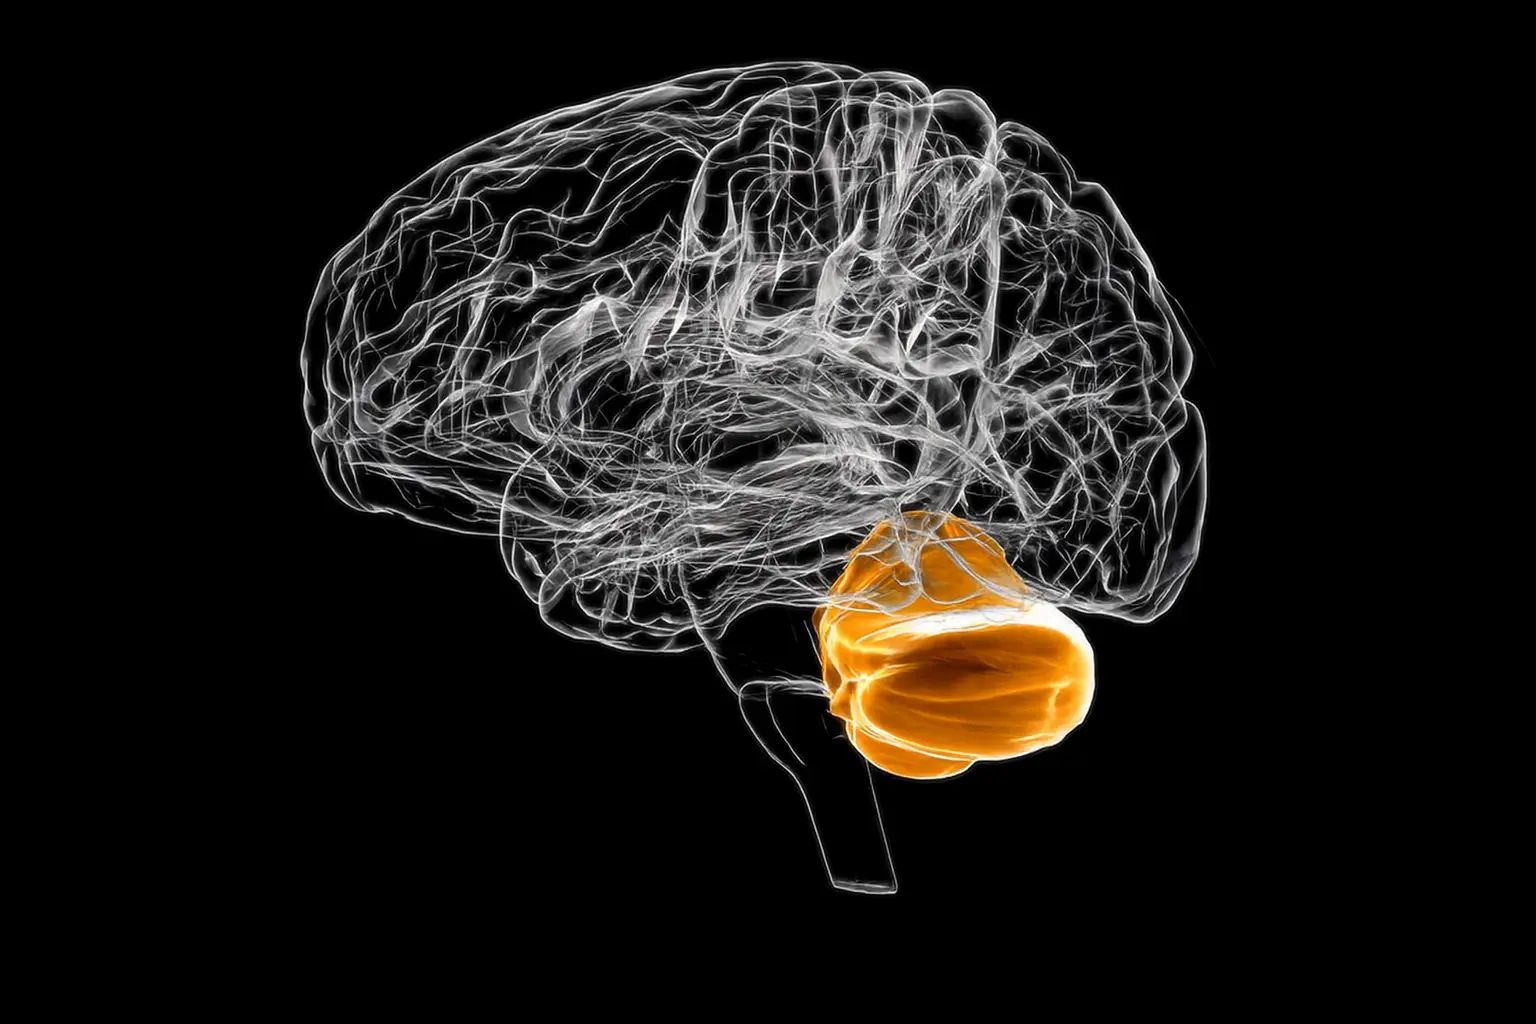

The Nodulus Technique: Precision Strategies for Visual-Labyrinthine-Otolthic Recalibration

A 15-hour, two-day intensive exploring nodulus-centered vestibular integration, translational VOR, gravity perception, and precision rehabilitation strategies for complex neurological patients.

The Cerebellum & Vestibular System

Throughout the module, clinicians will learn to assess, diagnose, and manage a variety of cerebellar and vestibular dysfunctions.